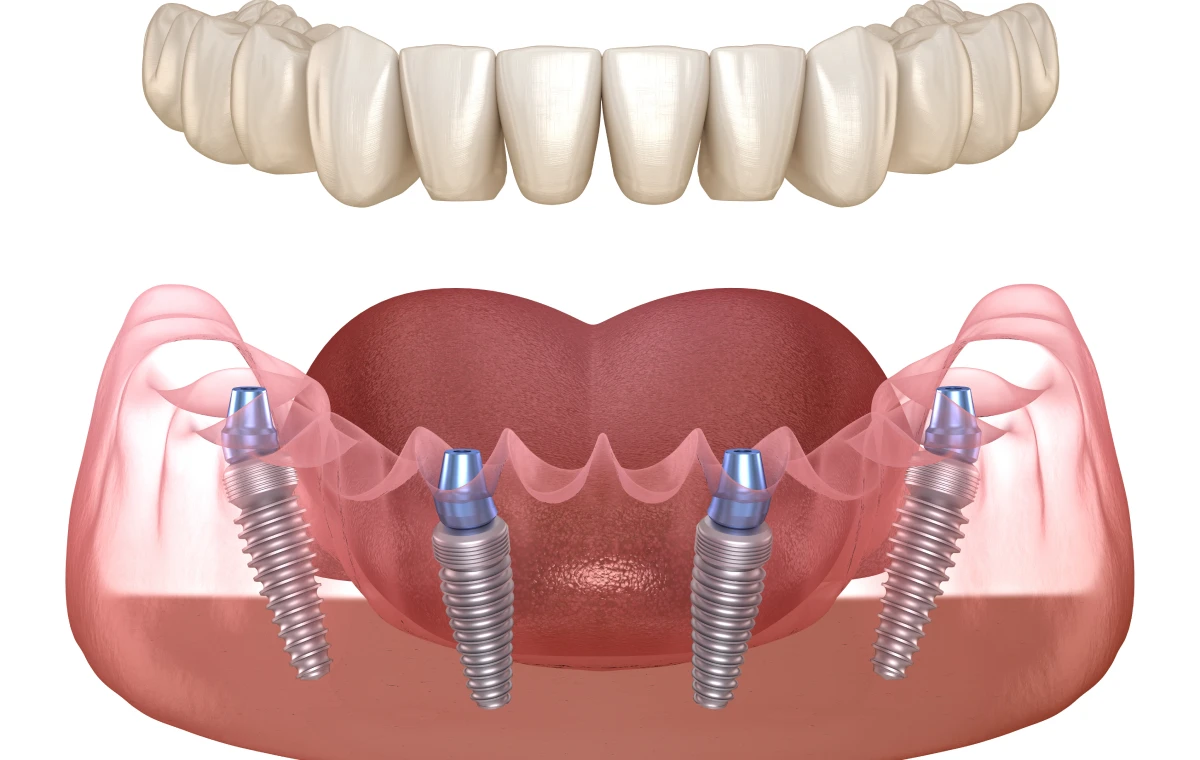

Le protocole All-on-6 est aujourd’hui reconnu comme une approche de choix en implantologie pour les patients édentés. Il consiste à poser six implants dentaires pour soutenir une prothèse fixe complète.

Le terme All-on-6 signifie « tout sur six ». Il décrit une réhabilitation implanto-portée où une prothèse fixe complète repose sur six implants. Les implants, insérés dans l’os maxillaire ou mandibulaire, agissent comme des racines artificielles. Ils soutiennent une arcade complète de dents artificielles conçues pour restituer une fonction masticatoire et un sourire esthétiques.

Sous anesthésie locale, six implants en titane sont posés. Leur répartition est optimisée : quatre implants dans la zone antérieure et deux implants postérieurs pour équilibrer les forces.

La prothèse finale est fabriquée sur mesure en céramique, en zircone ou en résine renforcée. Elle est fixée solidement aux six implants.